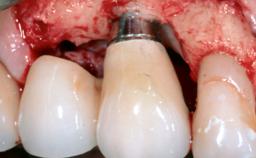

Treatment of Peri-Implantitis at a Zirconia Implant

Due to their promising clinical performance, zirconia implants have recently become popular alternatives to titanium implants, particularly for areas with high esthetic demands (Holländer and coworkers 2016; Roehling and coworkers 2016; Lorenz and coworkers 2019). However, regardless of the reported high survival and success rates, zirconia implants were affected by peri-implant diseases over the short observation period, suggesting the importance of treating peri-implant diseases at zirconia implants (Becker and coworkers 2017). In their case, Frank Schwarz and Ausra Ramanauskaite present 3-year results following mechanical debridement alongside Er:YAG laser monotherapy.